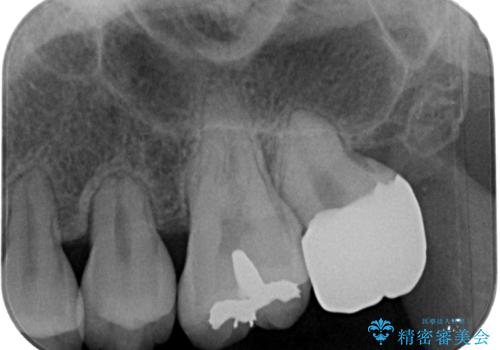

セラミッククラウンの適合はレントゲン写真からも分かる通り、境界がぴったりと合った、高適合のものとなりました。